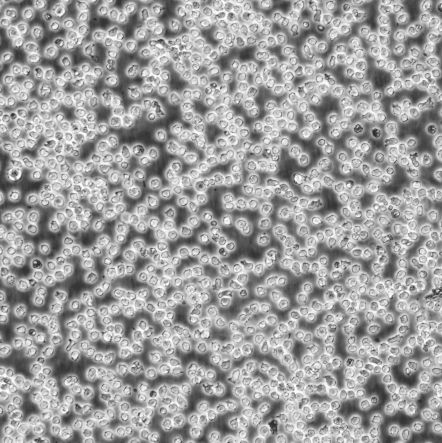

Kasumi-2_儿童急性B淋巴细胞白血病细胞

细胞名称:Kasumi-2_儿童急性B淋巴细胞白血病细胞

生长特性:悬浮生长

细胞形态:淋巴母细胞样

细胞规格:1 X 106cells/T25或1 mL冻存管

培养条件:90% RPMI 1640 + 10% h.i. FBS